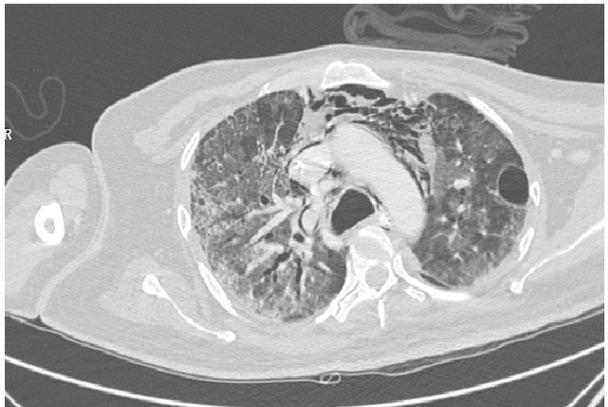

Clinically, there was a suspicion of pneumomediastinum, so rather than having a chest X-ray normally undertaken after intubation to confirm the cause of respiratory distress and rule out pneumothorax, an emergency high-dose contrast-enhanced computed tomography (CECT) was carried out. This showed an extensive mediastinal emphysema and pneumomediastinum. (Fig. 1B, C)

An axial section of the high resolution computed tomography chest image in a lung window showing Mediastinal emphysema (pneumomediastinum)